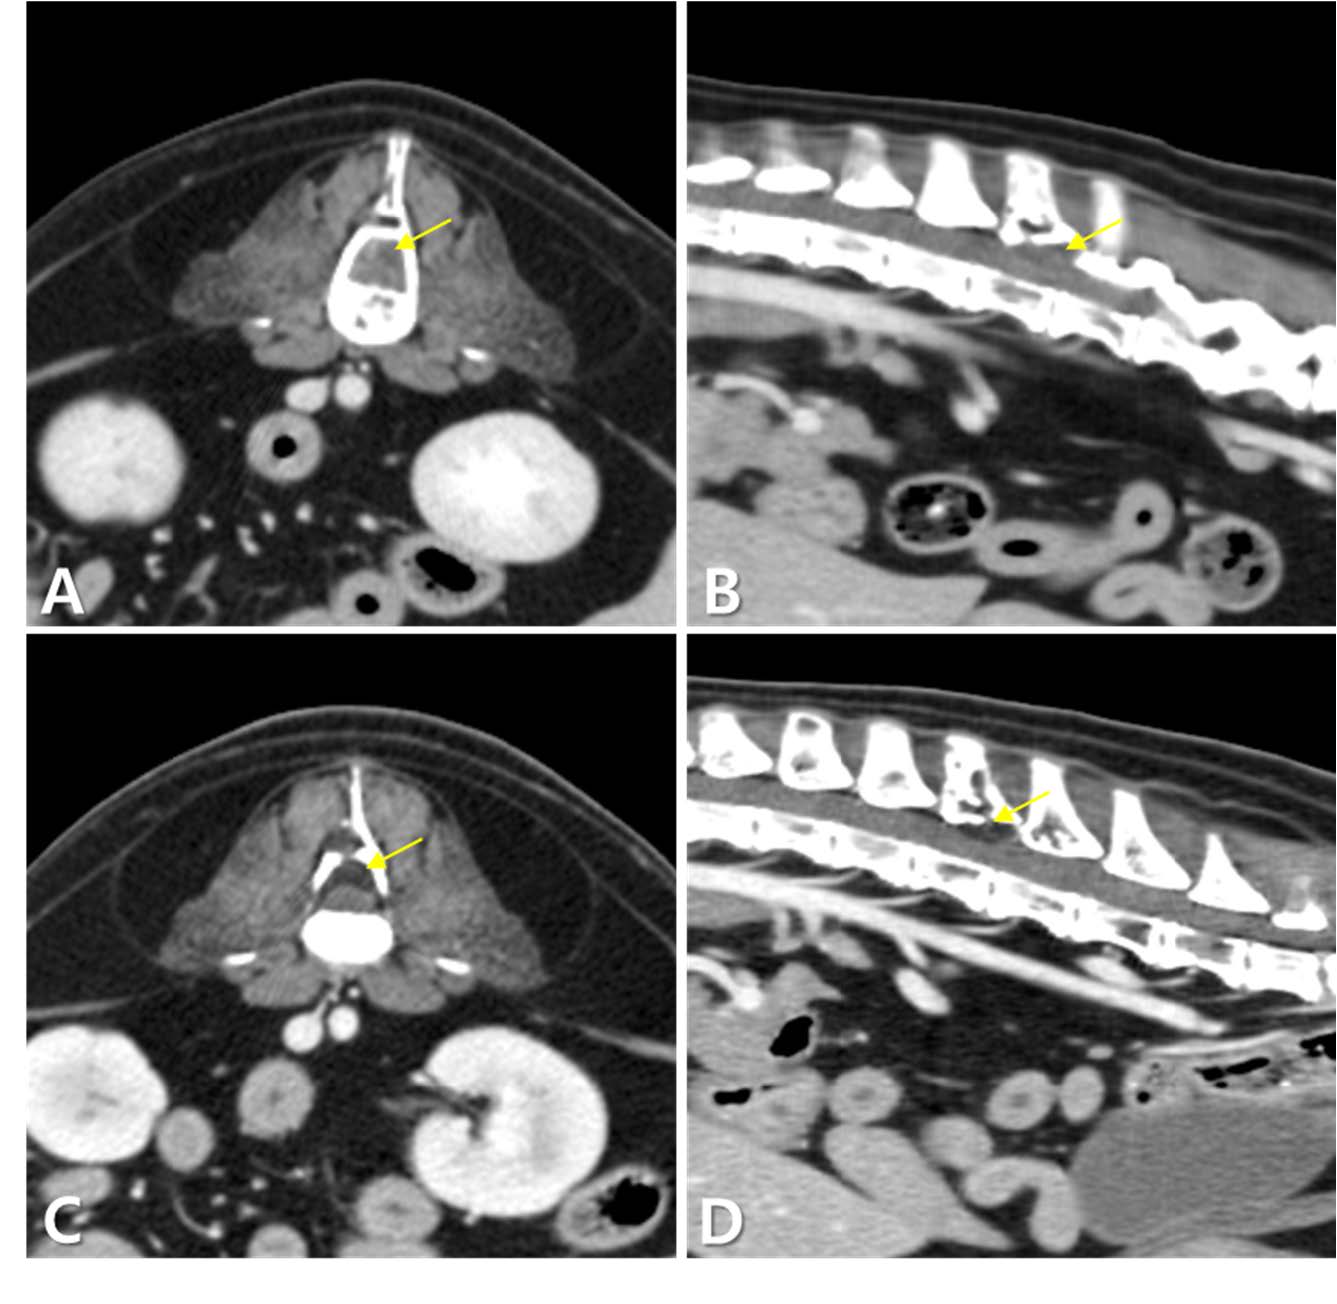

↑ CT结果。在横断面(未增强)图像上,L3水平肿块(箭头)和椎体骨溶解(A)。在胸椎和腰椎的多个区域观察到低密度区域(未增强)(箭头)(B)。在髂骨(箭头)(C)和耻骨(箭头)(D)区域发现骨溶解病变(增强后)。纵隔淋巴结(箭头)(E)和肝脏(箭头)(F)显著肿大(增强后)。

↑ L3-L4椎体水平肿块的增强CT图像,放疗前(AB)和放疗后(CD)。(AB) 放疗前的图像显示软组织密度肿块(箭头),压迫脊髓背侧。(CD) 放疗后的图像显示肿块(箭头)已转变为脂肪密度,体积显著减小,压迫得到缓解。